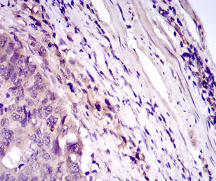

IHC    1/200 - 1/1000